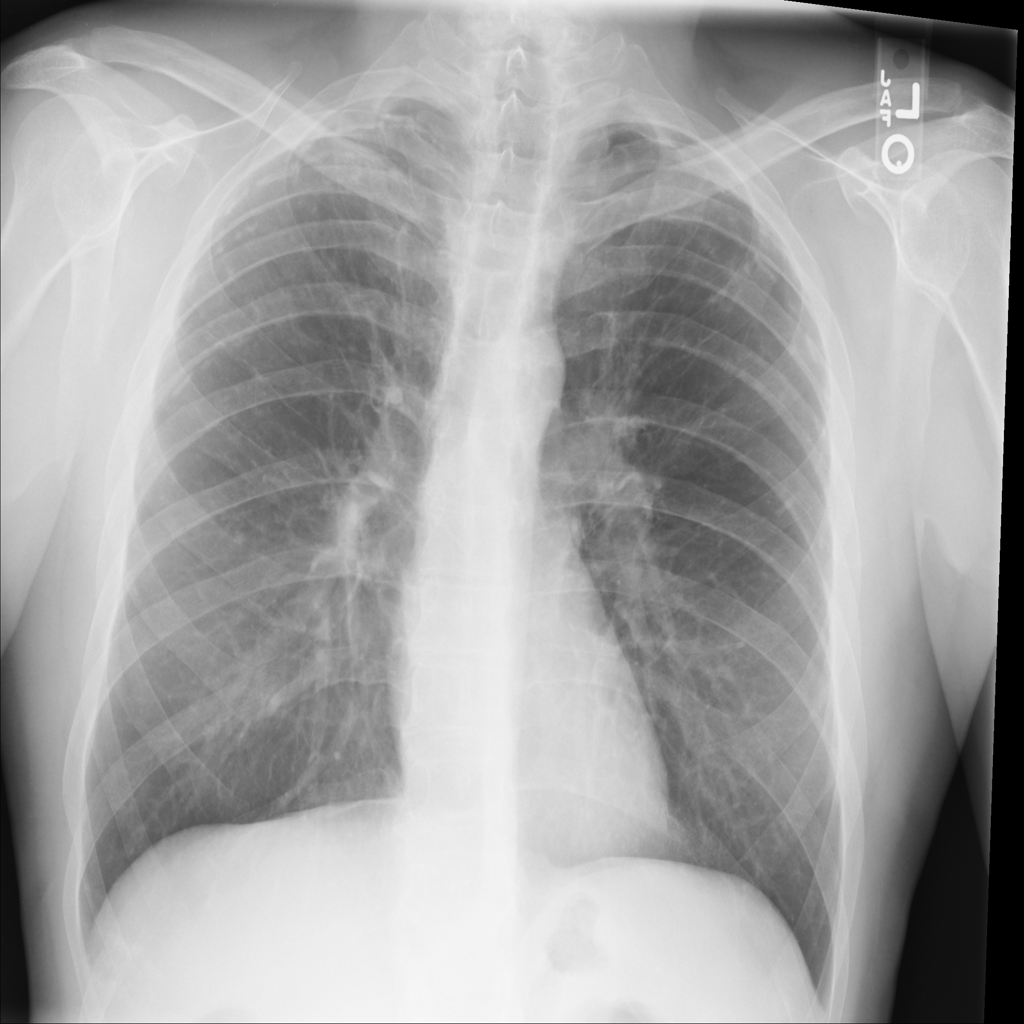

PAT-1F50 · IMG-000Fibrosis

PAT-1F50 · IMG-000

PA